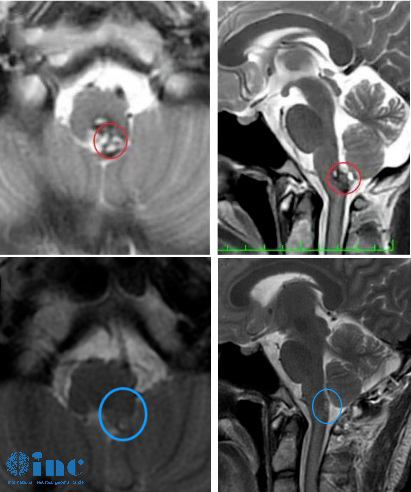

◉患者情况:2022年9月8日19岁的阿朔出现无明显诱因的头痛和晕胀感,从颞侧到枕后。10月10日于苏州独墅湖医院行颅脑核磁提示延髓异常信号,考虑海绵状血管瘤。

◉治疗过程:在2022中德学术交流-INC巴特朗菲教授示范国际疑难脑瘤手术直播,INC旗下的国际神经外科教授德国巴特朗菲教授受邀围绕“脑干海绵状血管瘤的手术”做课程演讲,并进行线上线下延髓手术示范直播。手术顺利全切阿朔延髓海绵状血管瘤,直播观看人次达7000多,除了神经外科医生观看外,还有即将接受教授手术的患者家属共同观看。

◉术后情况:术后1天巴教授ICU查房,阿朔意识清楚、对答如流、四肢活动灵活,随即出ICU;术后5天,可正常站立、行走;术后8天,阿朔状态很好,正逐步回归正常生活。术后一个月,阿朔回到大学校园,回归正常的学习和生活。术后3个月,阿朔还接受了INC专访,交流自己的治疗经历,希望能够帮到更多的人。